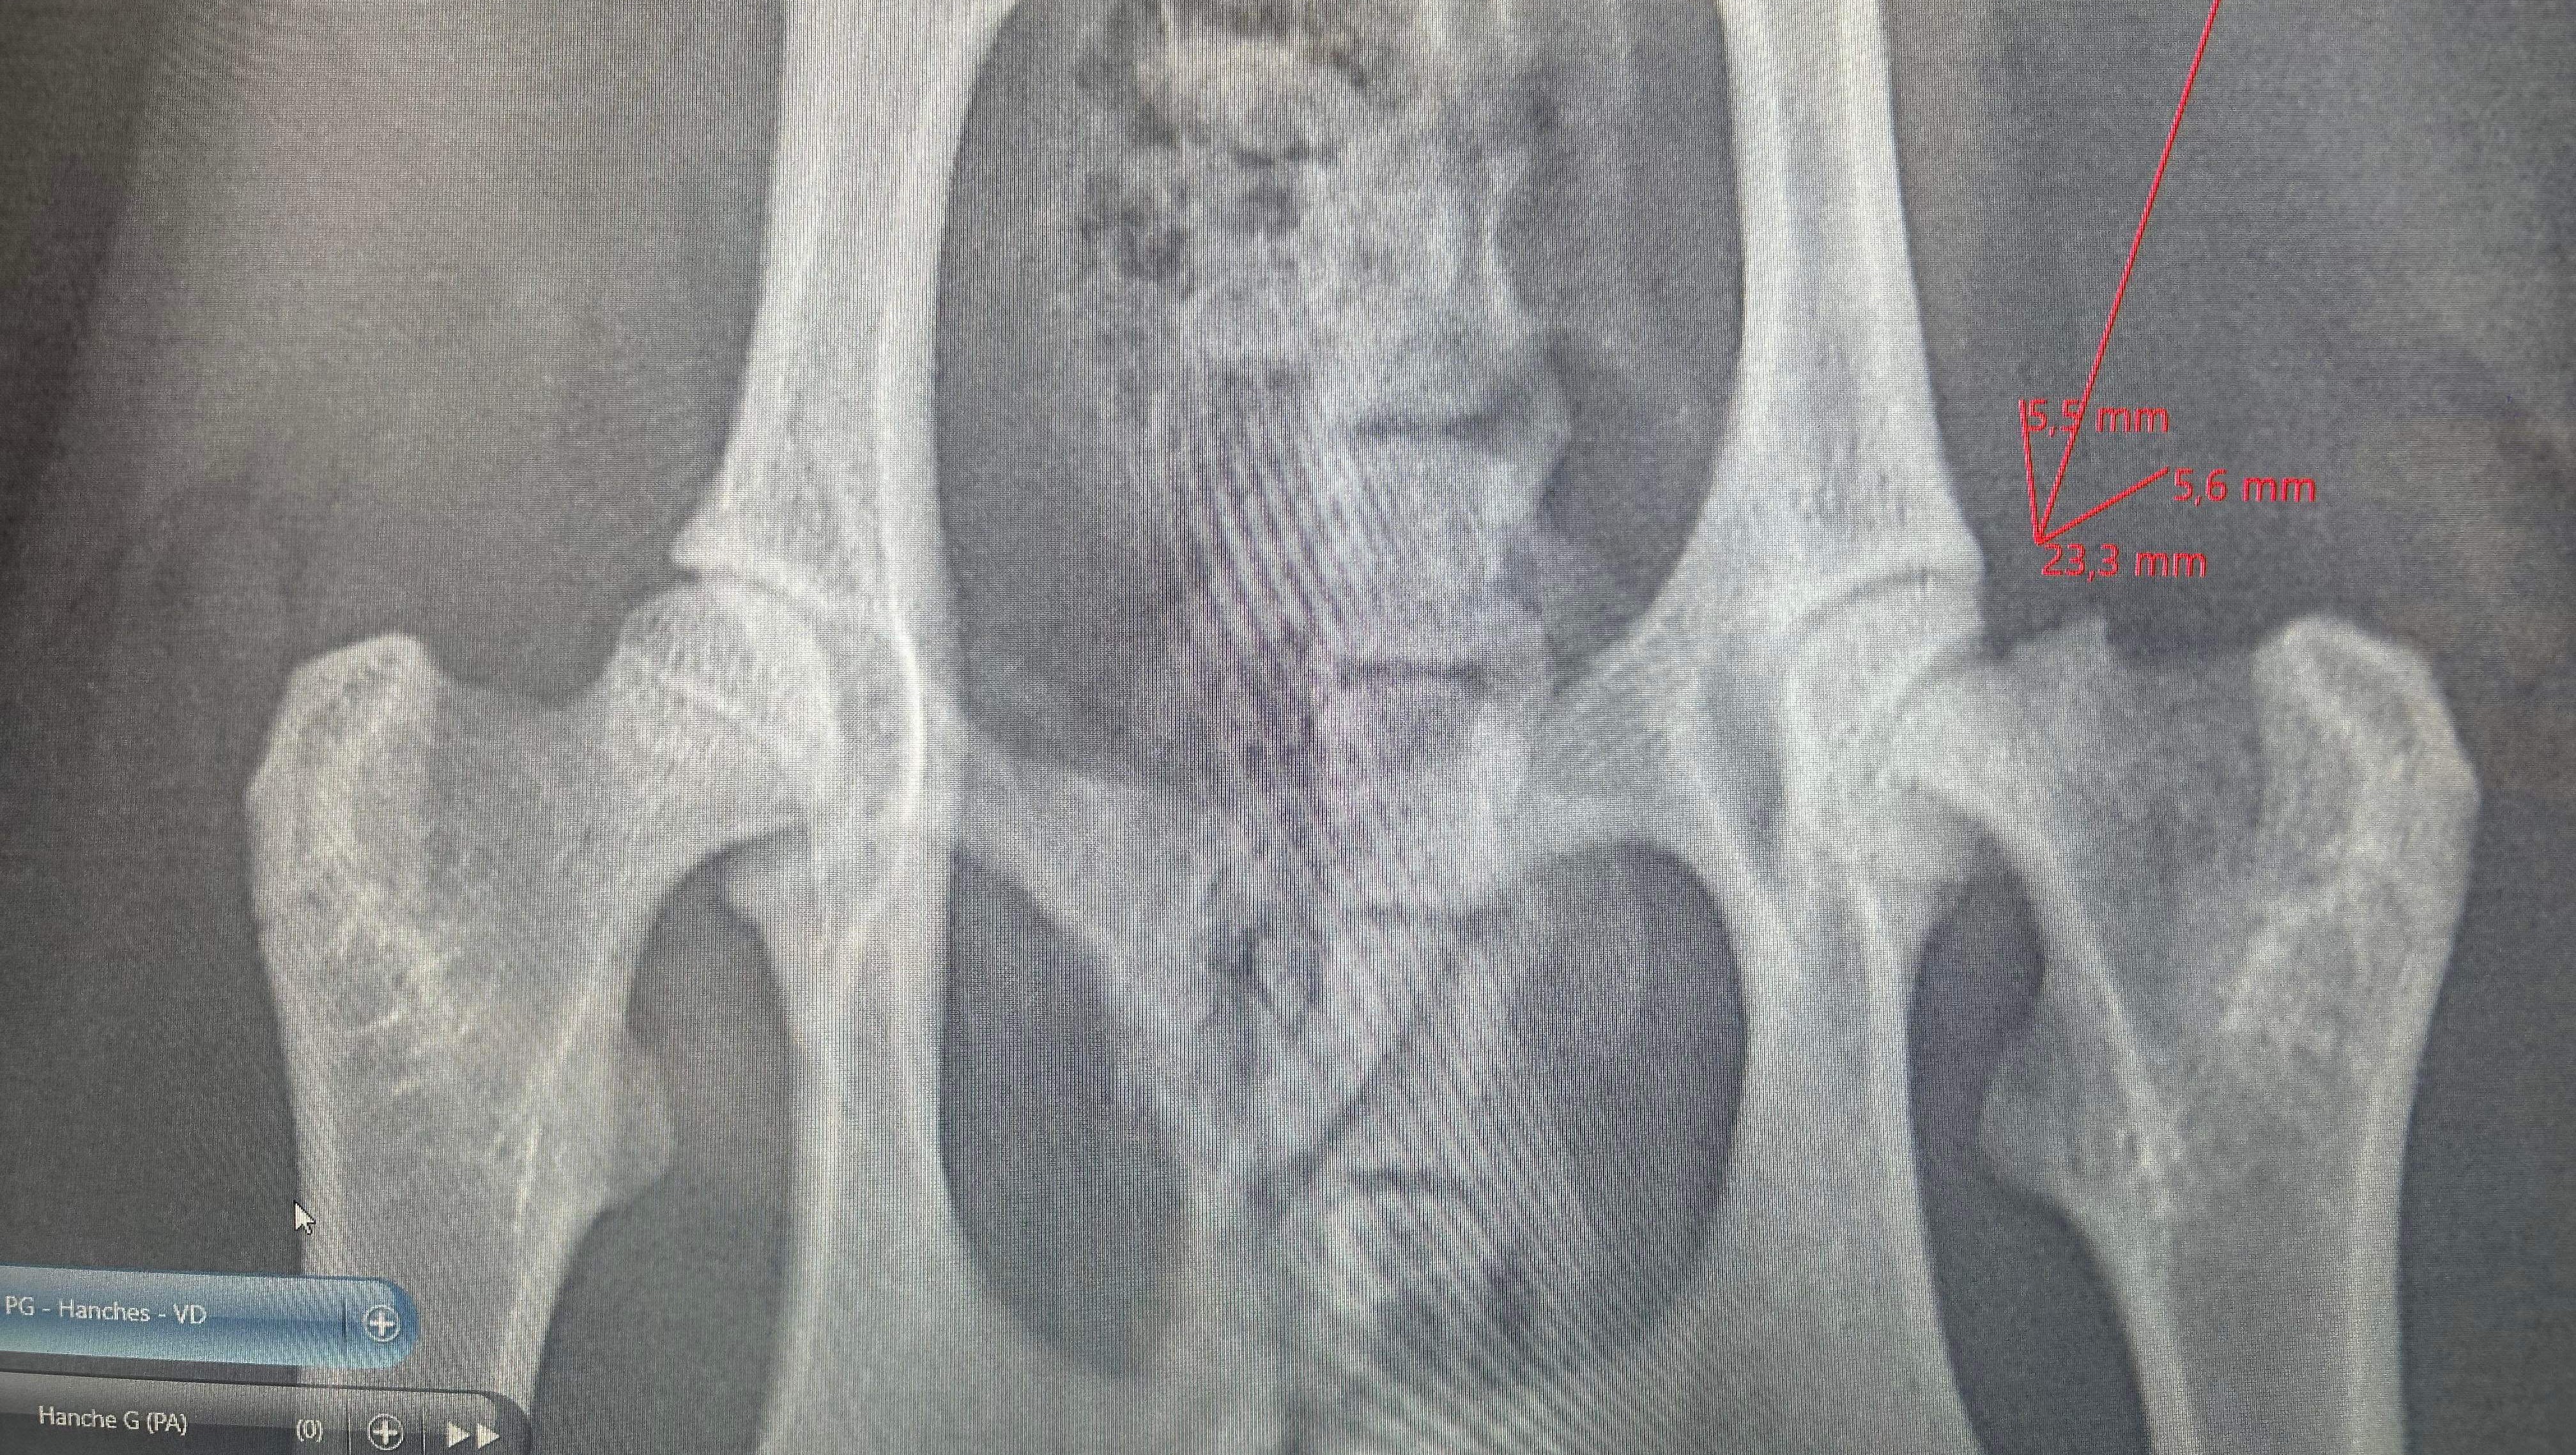

Je me suis rapidement rendu compte qu’il ne pouvait pratiquement plus marcher. Après une visite chez le vétérinaire d’urgence, on m’a annoncé qu’il avait la hanche fracturé et que les coûts s’élevaient à pratiquement 3000$ pour l’opération. (Opération 2883$ + médicament, + consultation donc environs 3000$ total)

radiographie de la hanche